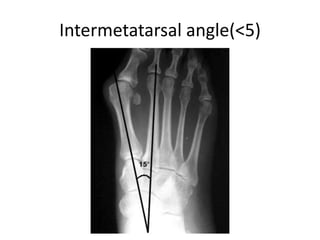

Anteroposterior view

• Talocalcaneal angle

• Calcaneal-second metatarsal angle

• Talus –first metatarsal angle

• Intermetatarsal angle

AP radiograph: Talo-Calcaneal angle

• Lines drawn through

center of the long axis of

talus (parallel to medial

border) and through the

long axis of calcaneum

(parallel to lateral border),

and they usually subtend an

angle of 30-45°.

• decreased in a varus foot

and increased in a valgus

hindfoot

Axis of the second

metatarsal diaphysis

Axis of the calcaneus

15º : Normal value

> 15º : Pes adductus

Talus –first metatarsal angle

Intermetatarsal angle(<5)